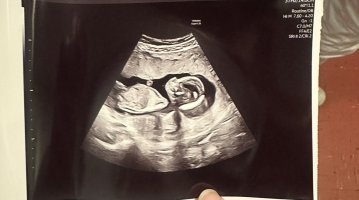

Så morro med 3DTUL idag, ble flytta fra 13+0 til 13+3Fikk ikke sett kjønn, men alt så helt perfekt ut!

![]()